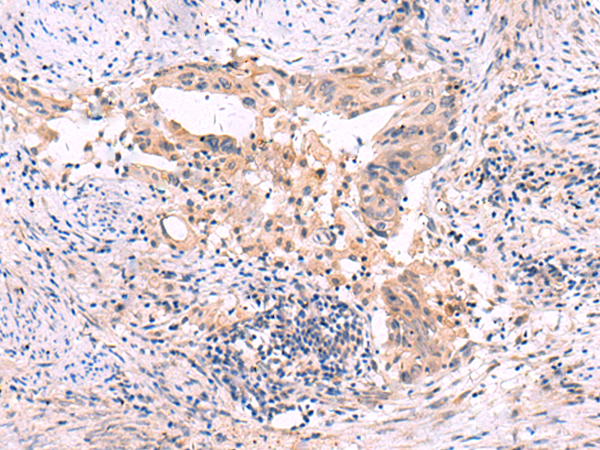

IHC positive control: |

Human cervical cancer |

IHC Recommend dilution: |

30-150 |